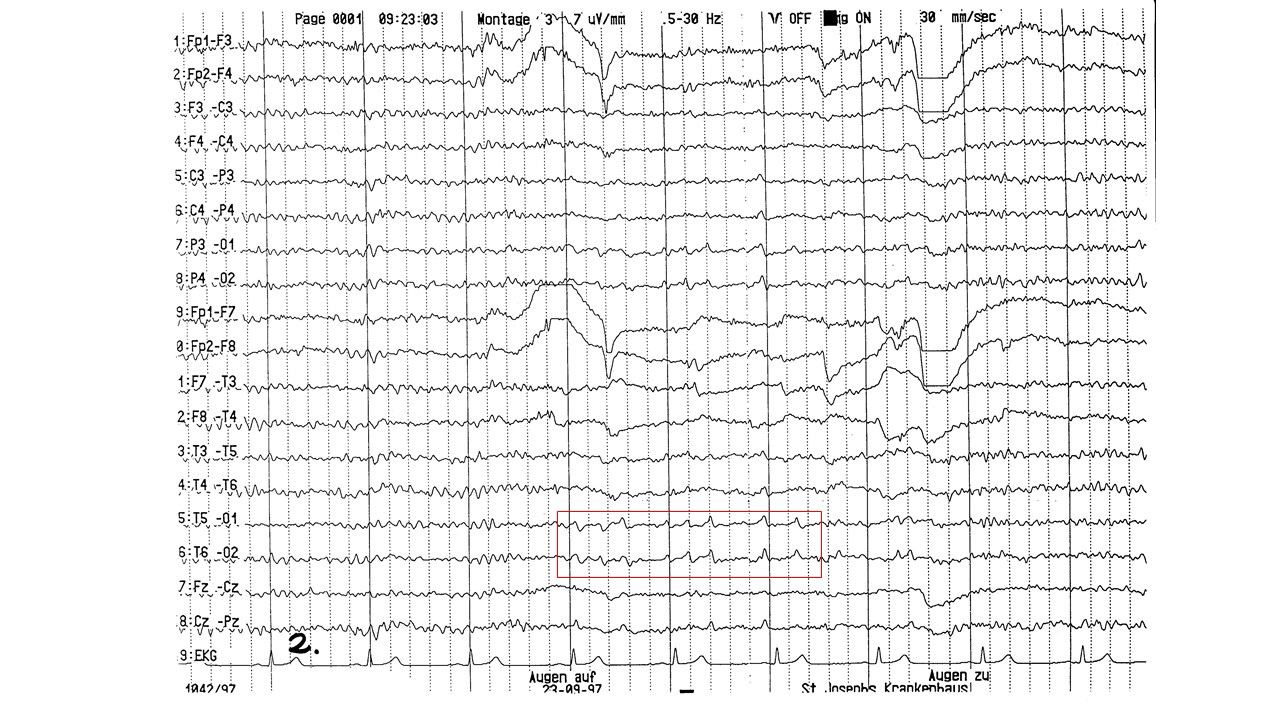

folie531.jpg